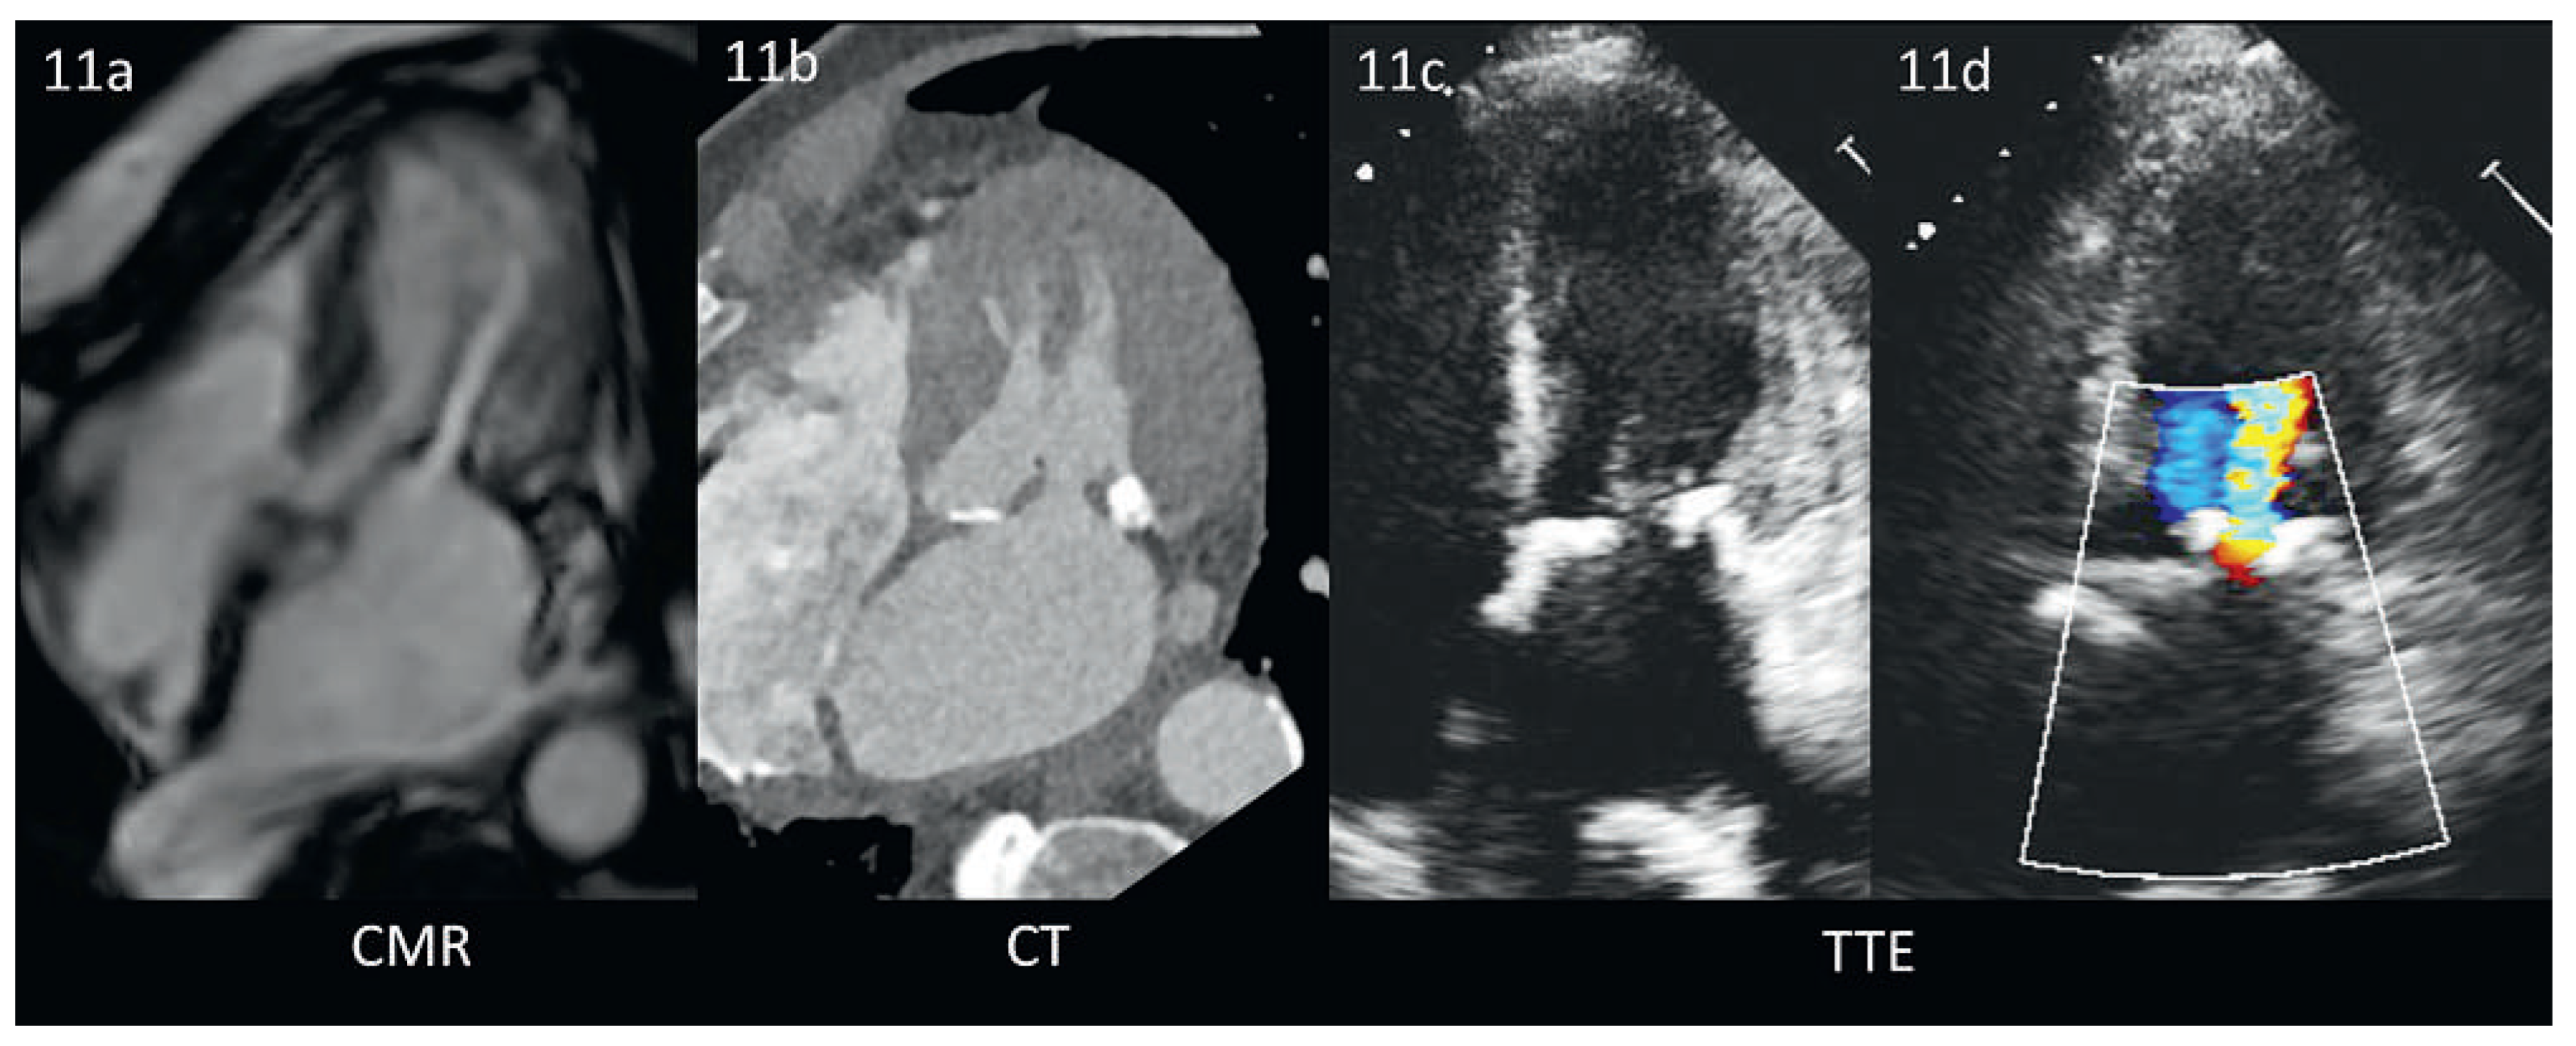

Abbildung 9. Leichte funktionelle Mitralinsuffizienz, Vergleich CMR und TTE am selben Patienten. Die 4–Chamber-View erlaubt die Beurteilung der Ventrikelgeometrie, der Myokardtextur sowie des Schweregrades der Mitralinsuffizienz (hier leicht). Echokardiographisch (9a) ist insbesondere die apikale und laterale Endokardgrenze schwer zu erkennen, was bei der CMR (9b) optimal zur Darstellung kommt. In der CMR kann auch bei einem dilatierten Herz gleichzeitig der rechte Ventrikel (und die hier leichte Trikuspidalinsuffizienz) gezeigt werden. Bei der Echokardiographie muss dies meist in mehreren Schritten geschehen, um eine genügende zeitliche Auflösung zu bewahren.

Das bevorzugte bildgebende Verfahren zur Diagnose einer durch eine KMP verursachte Mitralinsuffizienz ist die Echokardiographie [41]. Die Grösse des linken Ventrikels sowie die exakte Störung seiner Geometrie können dargestellt werden (Abbildung 9a). Ebenfalls erkennbar ist das Ausmass der Anulusdilatation und des Tetherings der Sehnenfäden. Zudem können die «tenting height» und «tenting area» gemessen werden, welche für die chirurgische Sanierung eine prognostische Aussagekraft besitzen [42]. Die Quantifizierung der Mitralinsuffizienz birgt die eingangs erwähnten Schwierigkeiten. Gewisse Formen der KMP ergeben ein typisches, in der Echokardiographie gut zu erkennendes Myokardmuster ab (z.B. Amyloidose).

Für echokardiographisch unerklärte Formen kann in einigen Fällen die CMR weiterhelfen, welche eine zusätzliche Gewebecharakterisierung erlaubt [43]. Die CMR bietet insbesondere die Möglichkeit, die myokardiale Ursache der Mitralinsuffizienz weiter zu evaluieren: Myokardiale Ödeme, kleinere und grössere Fibroseherde sowie das Ausmass von Narben. In der Regel ist zudem die räumliche Auflösung exzellent und er-möglicht insbesondere bei schlechter Schallqualität die Quantifizierung der Ventrikeldimensionen (Abbildung 9b), der LV-Funktion sowie des Schweregrades [44], der‚ tenting area’ und der Anulusfläche [35].